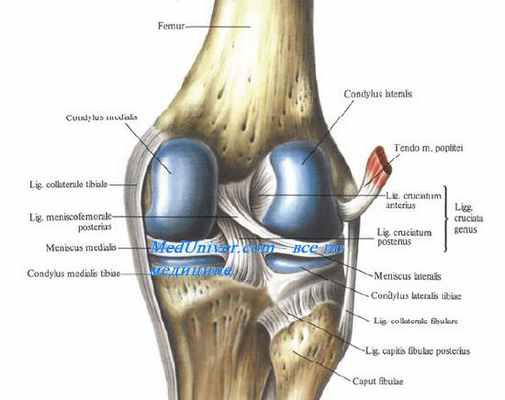

Снаружи капсулу коленного сустава укрепляют коллатеральные связки коленного сустава, lig. collaterale tibiale (от epicondylus medialis бедра до края tibiae) и с латеральной стороны lig. collaterale fibulare (от epicondylus lateralis до головки fibulae). Последняя связка имеет форму шнурка, который не срастается с суставной сумкой, отделяясь от нее жировой клетчаткой.

На задней стороне капсулы коленного сустава находятся две связки, вплетающиеся в заднюю стенку, — lig. popliteum arcuatum и lig. popliteum obliquum.

На передней стороне коленного сустава располагается сухожилие четырехглавой мышцы бедра, которое охватывает patella, как сесамовидную кость, и затем продолжается в толстую и крепкую связку, lig. patellae, идущую от верхушки надколенника вниз к tuberositas tibiae. Эта связка отделяется от суставной сумки жировой клетчаткой. По бокам patella боковые расширения сухожилия четырехглавой мышцы образуют поддерживающие связки надколенника, так называемые retinacula patellae (laterale et mediale). Они удерживают надколенник во время движения.

Кроме внесуставных связок, коленный сустав имеет две внутрисуставные связки коленного сустава, называемые крестообразными, ligg. cruciata genus.

Передняя крестообразная связка коленного сустава, lig. cruciatum anterius, соединяет внутреннюю поверхность латерального мыщелка бедра с area intercondilaris anterior tibiae.

Задняя крестообразная связка коленного сустава, lig. cruciatum posterius, идет от внутренней поверхности медиального мыщелка бедра к area intercondylaris posterior большеберцовой кости.

Они прочно соединяют между собой бедренную и большеберцовую кости, обеспечивая функции коленного сустава.

Крестообразные связки коленного сустава лежат частично вне синовиальной оболочки капсулы коленного сустава. Синовиальная оболочка с мыщелков бедра переходит на переднюю поверхность крестообразных связок и, охватывая их спереди и с боков, оставляет их задние отделы непокрытыми. Благодаря такому ходу синовиальной оболочки латеральный и медиальный отделы коленного сустава разобщены. Кроме того, те же связки делят полость сустава на переднюю и заднюю части, препятствуя в случае воспаления проникновению гноя из одной части в другую до определенного времени.